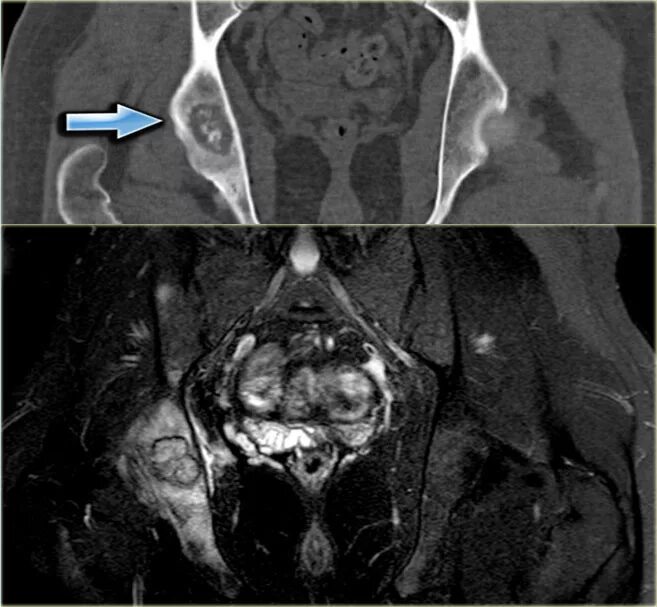

Метастазы костей мрт